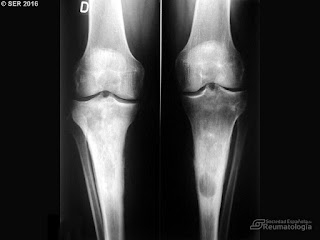

- Osteosclerosis simétrica de los huesos largos: se comprueba mediante una biopsia ósea.